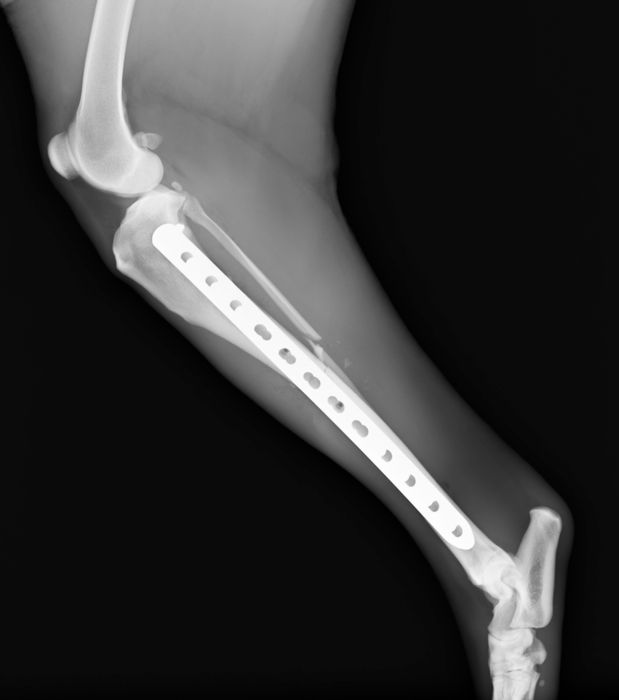

●骨プレート

ステンレス製もしくはチタン製の金属の板(プレート)と骨ネジ(スクリュー)を使用して固定を行います。

●髄内ピンと骨プレートの併用(プレート-ロッド併用法)